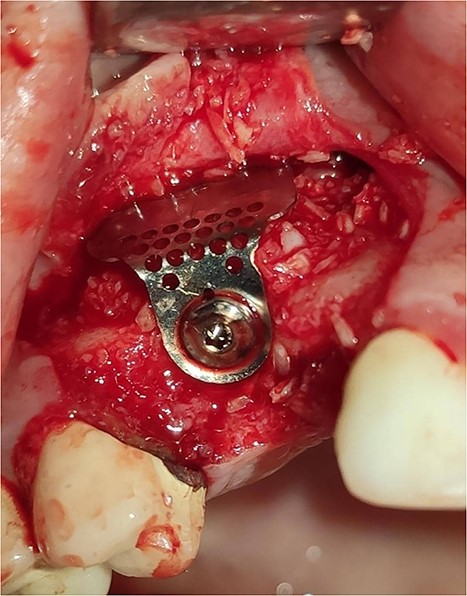

Under local anesthesia with 4% articaine solution, a full-thickness flap was raised to expose the alveolar ridge. The initial point was marked with a point drill. The implant site was first prepared with a 2.2 mm pilot drill, and then with a 3.3 mm drill. After preparing the implant bed, we noticed the disappearance of the coronal and middle third of the buccal wall, exactly as planned. A submerged implant system (INNO submerged implant; Cowellmedi Inc, South Korea) was inserted according to the manufacturer’s instructions (Fig. 1). The insertion torque value was 33 N.cm. several perforations were prepared at the buccal side of the recipient bone bed using a small round bur for better blood supply. An allogeneic bone graft material (Cortical Cancellous powder; TRCIR Co, Iran) was used to reconstruct the buccal plate. A prefabricated L-shaped titanium mesh has been adapted to fit the shape of the alveolar ridge to be reconstructed, and it was fixed to the implant with a cover screw (Fig. 2). The flap was mobilized to permit a tension-free primary closure, was closed with 4–0 silk sutures. Sutures removal was done after 1 week. The surgical sites were left to heal for 6 months.

Reconstruction of the buccal plate using an allogeneic bone graft material and a prefabricated L-shaped titanium mesh. The titanium mesh was fixed to the implant with a cover screw.